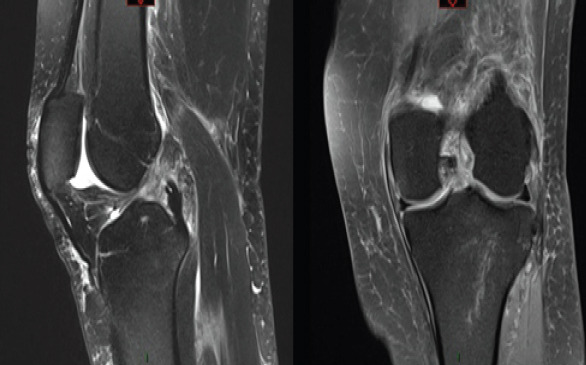

Case report: The authors present a case of a 60-year-old Caucasian female who developed a femoral-sided cyclops lesion after ACL repair. After initially achieving full range of motion (ROM) post-surgery, the patient later experienced a palpable clunk and extension loss 3-months postoperatively. While magnetic resonance imaging (MRI) was unremarkable, subsequent arthroscopy confirmed the diagnosis, leading to successful lesion excision and notchplasty.